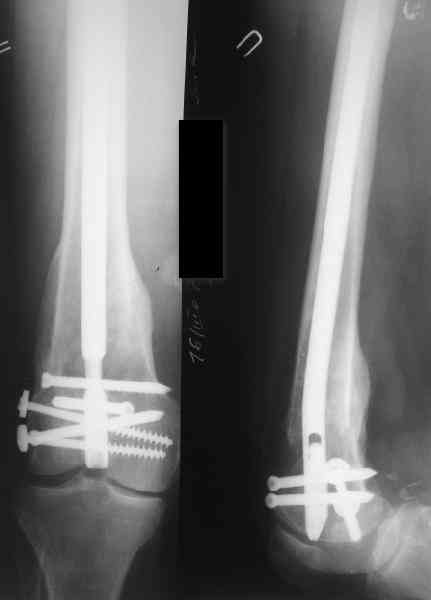

В приложении как раз видна эволюция использововшихся у нас большеберцовых гвоздей. Первый - дизайн как у UTN, второй - разнесены 45 градусные отверстия (зачем их вообще изначально так нелепо на одном уровне сделалм???), третий - убрано сиавшее лишним статическое отверстие, Herzog's bend перемещен более проксимально.